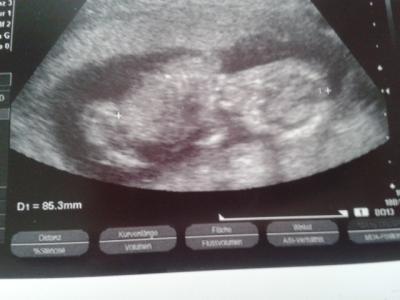

Mein Baby bei SSW 16. Hat nur die SSL gemessen. 8,5 cm.